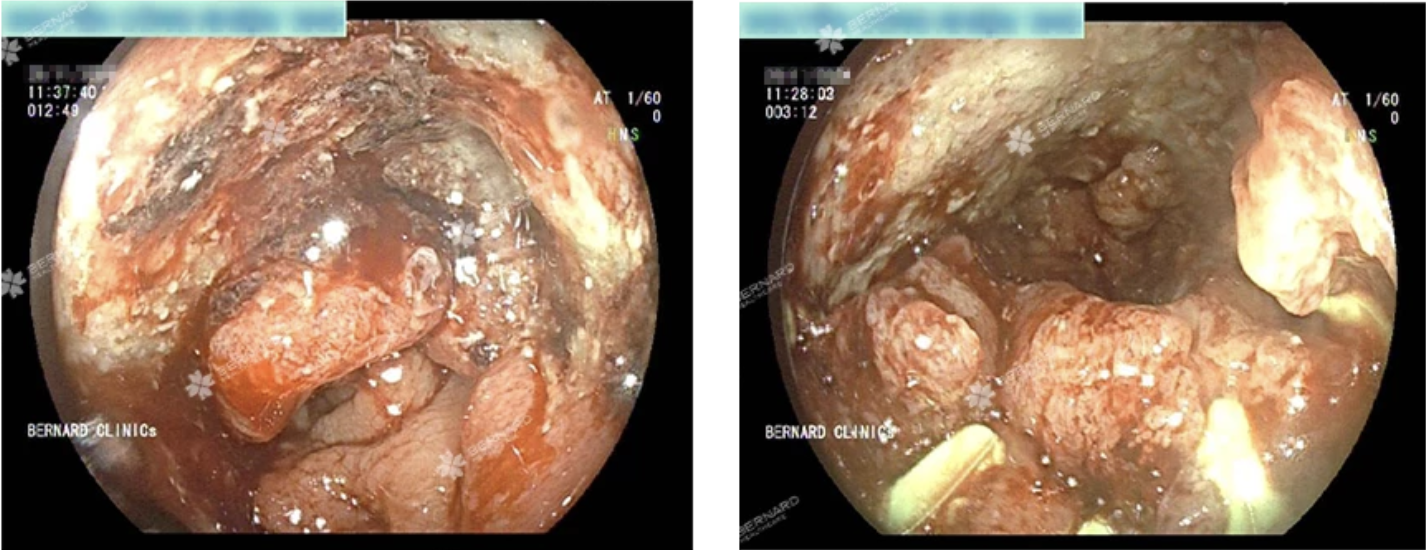

Tại đây, bác sĩ đã chỉ định thực hiện các xét nghiệm chuyên sâu, trong đó có nội soi đại trực tràng bằng ống mềm không đau. Kết quả cho thấy một khối u sùi tại đoạn trực tràng cách hậu môn khoảng 14 - 18cm, nghi ngờ ác tính. Sinh thiết ngay trong quá trình nội soi xác nhận: ung thư tuyến biệt hóa trung bình.

Chụp CT sau đó ghi nhận tổn thương lan rộng, dày thành trực tràng và có hạch quanh khu vực. Nhận định đây là ca bệnh tiến triển, các bác sĩ Bernard đã lập tức hội chẩn liên chuyên khoa Nội - Ngoại - Chẩn đoán hình ảnh và chuyển bệnh nhân đến bệnh viện chuyên khoa ung bướu để tiếp tục điều trị.